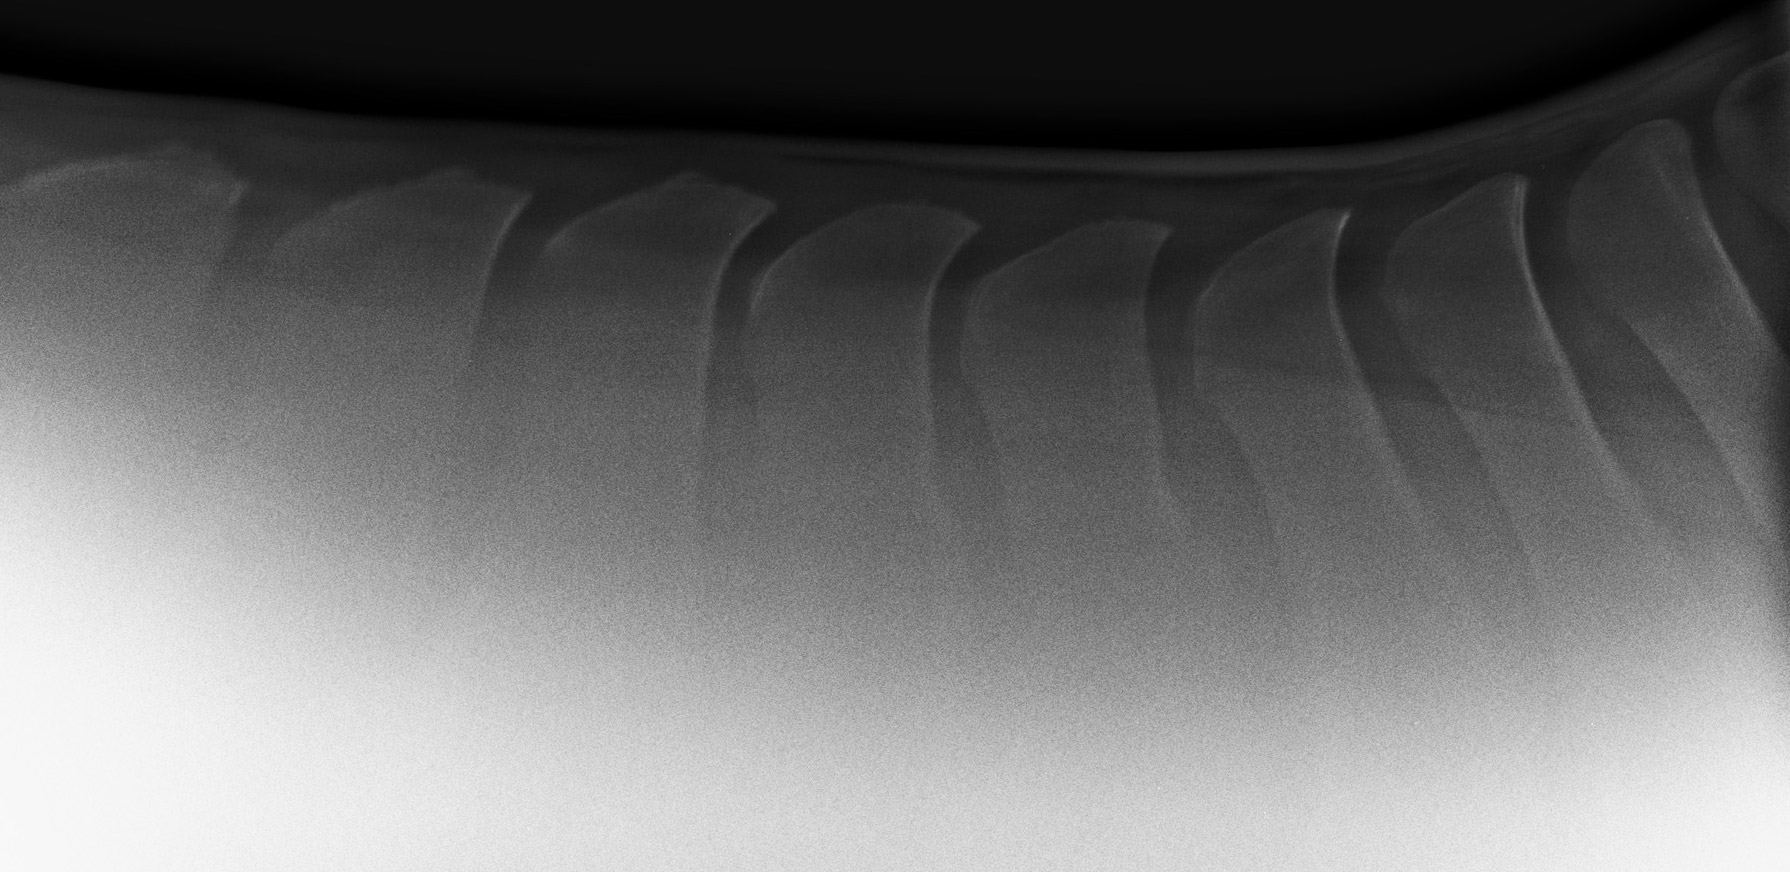

Aufnahme der Dornfortsätze der Brustwirbel im Bereich der Sattellage